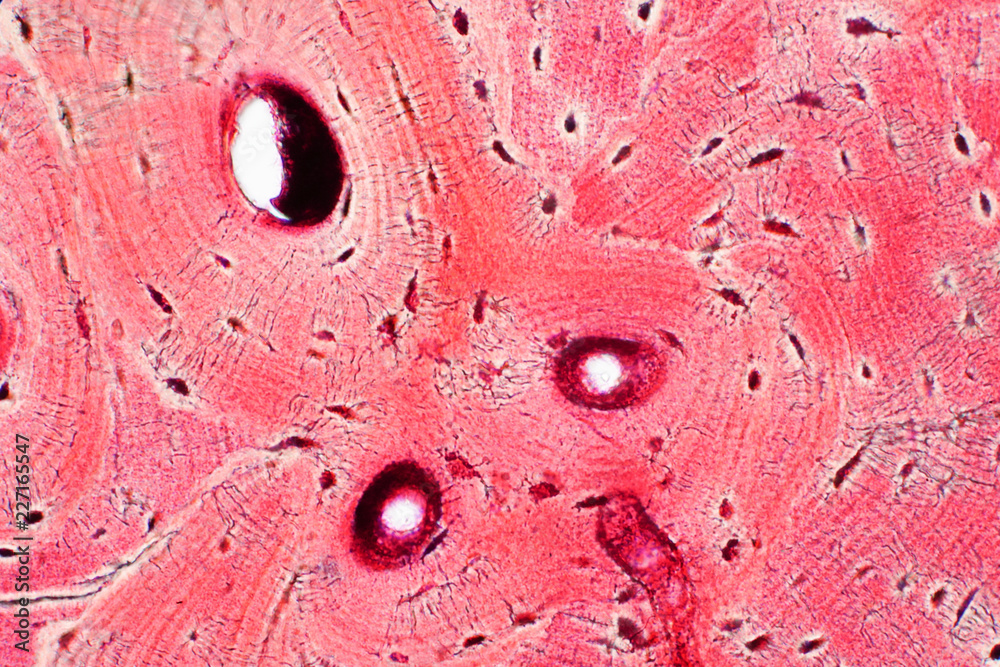

Структура грубоволокнистой костной ткани: наглядные примеры